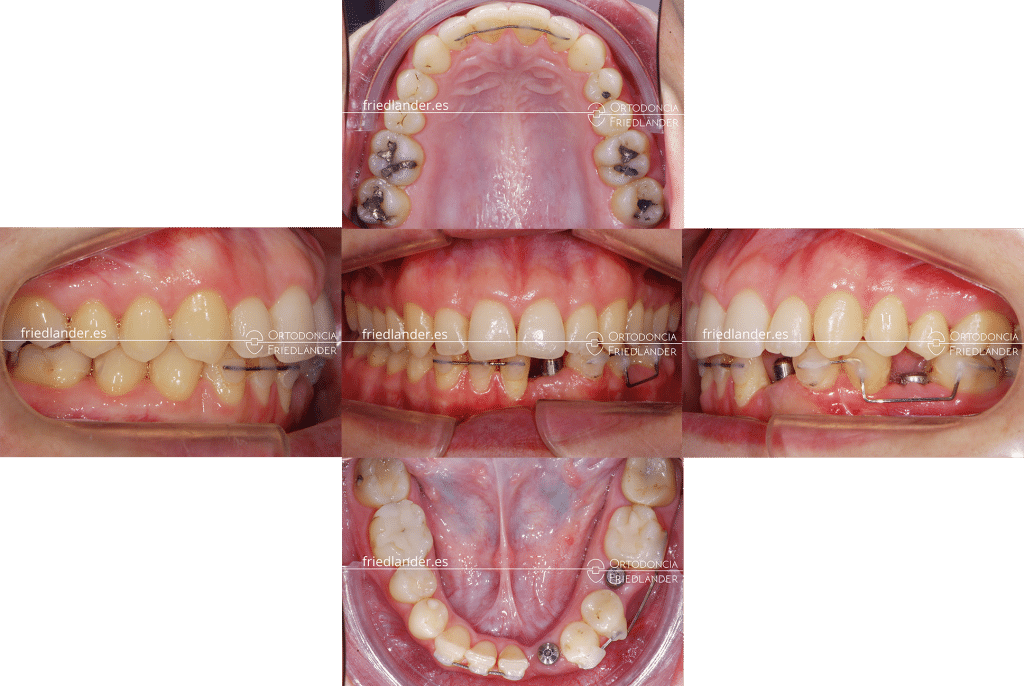

Después de unos 22 meses de tratamiento de ortodoncia, aproximadamente, hemos podido abrir espacio en la zona posterior para un implante, hemos cerrado el espacio ligeramente en zona anterior y hemos dejado un pequeño espacio para poder hacer los incisivos inferiores un poco más anchos. En la siguiente imagen se puede ver los espacios creados con los implantes correspondientes colocados. Los alambres que se ven en la imagen son retenedores temporales que evitan movimientos indeseados mientras se espera a la integración de los implantes (se llevan 3-4 meses).

Finalmente se colocan las coronas sobre los implantes y se realizan la reconstrucciones necesarias. El resultado final del tratamiento es bueno y la paciente acabó muy contenta.

Comparativa de antes y después con la boca abierta.